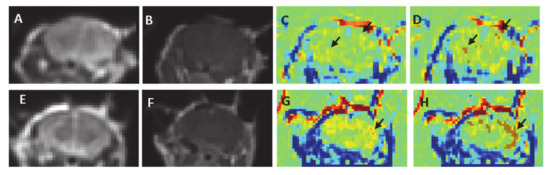

Figure 4.

Examples of T1-MRIs and their equivalent 30 min TRAMs for different treatment voltages. (A) T1-MRI obtained immediately post-contrast injection for sham (0 V) and for mice treated with 100 pulses at 100–300 V. No enhancement is visible in the brain parenchyma (B). TRAMs calculated by subtracting the first T1-MRI post-contrast injection from the 30 min T1-MRI, showing increased BBBd volumes (depicted yellow/red, mainly in the cortex) with increased treatment voltage.

No signs of edema, damage or bleeding were observed in any of the treated mice. Standard 3D T1-MRI obtained immediately post-contrast injection showed no clear enhancement in the brain parenchyma in any of the mice (Figure 3A,B,E,F). Nevertheless, the calculated TRAMs, which are sensitive to subtle BBBd, reveled significant BBBd which increased with the treatment voltage and with the number of pulses. The TRAMs showed contrast agent accumulation (depicted red) mainly in the cortical region, as predicted by the simulation (Figure 3G–H). The average volume of BBBd found for the sham group (0 V) was 6.08 ± 3.09 mm3 and the average intensity increase was 6.76% ± 0.2%. The pixels determined to represent BBBd by our analysis algorithm were sporadic pixels scattered in the brain resulting from noise. The average BBBd volume of the minimal treatment group (100 pulses at 100 V) was significantly larger than that of the sham group (39.10 ± 9.66 mm3, p < 0.02) and the disrupted volume was concentrated mainly in the cortex of the mice, as can be seen in Figure 3. The increase in signal intensity was also significantly higher than that of the sham group (13.73 ± 4.09, p < 0.009). These results suggest that subtle BBBd was obtained when applying 100 pulses at 100 V.

The dependency of BBBd volume and intensity on the applied voltage was studied in mice treated with 100 pulses at 100, 200 and 300 V (Figure 4). A linear regression was calculated to predict the effect of the applied voltage on the extent of BBBd. A significant regression equation was found (F(1, 19) = 85.60, p < 1.8 × 10−8) with r2 = 0.82. The results suggest that the applied voltage accounted for 82% of the variation in BBBd volume, a large size effect according to Cohen [38]. The prediction equation was BBBd(V) = 0.733 V–22.41, where V is the applied voltage. The results demonstrated a 336.7% increase in the average BBBd volume when the voltage was increased from 0 to 300 V, suggesting strong dependence on the voltage (Figure 5A). The dependency of BBBd intensity (increase in signal intensity over time) on the applied voltage was also studied using liner regression. BBBd intensity increased by 216.2% (from 6.76% ± 0.20% to 14.63% ± 1.75%) when the voltage was increased from 0 to 300 V.